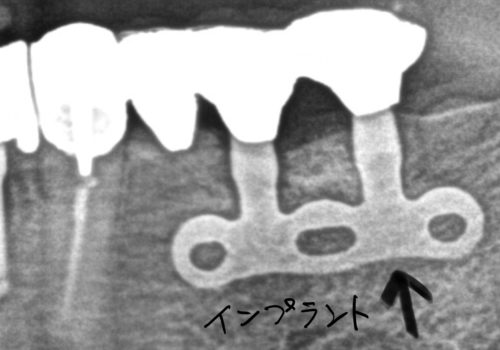

現在ではあまり使用されなくなった、インプラントのブレードタイプと呼ばれるものです

さらに、天然歯(自分の歯)と連結して、欠損を補っています

現在では選択しないものの、このインプラントは15年以上も口腔内で機能しています

インプラントは適正な配置で、適正にメインテナンスが出来ていれば、

入れ歯をせずによく噛める、良い材料だと考えています

もちろんこれは撤去の必要などはないと考えています